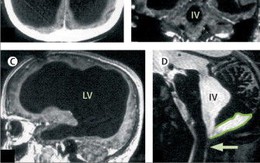

Kinh ngạc phát hiện người đàn ông gần như không có não, trong khoang sọ chỉ toàn chất lỏng vẫn sống bình thường: Nguyên nhân vì sao?

Bệnh nhân 44 tuổi có đầy đủ nhận thức như bao người dù mang bộ não khác thường.